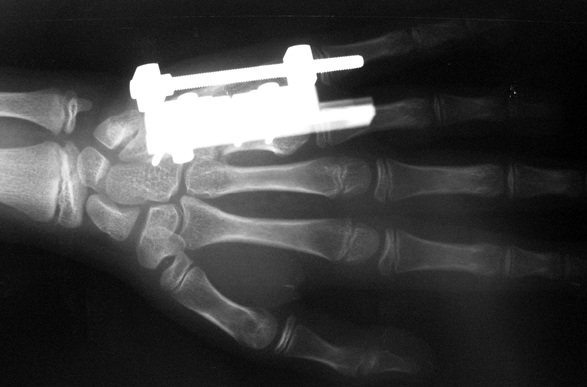

Doğuştan metakarp ve metatars kısalıklarının redavisi için pek çok teknik tanımlanmakla birlikte en çok akut uzatma sonrası kemik uçlarına greft konması ve distraksiyon osteogenezi (kallotasis) kullanılmaktadır. 1 cm.den daha fazla uzatma gereken olgularda kallotasis yöntemi önerilmektedir. Kliniğimizde de metatars ve metakarp uzatma için unilateral eksternal fiksatör ve sirküler eksternal fiksatör yardımıyla distraksiyon osteogenezi yöntemi tercih edilmektedir.